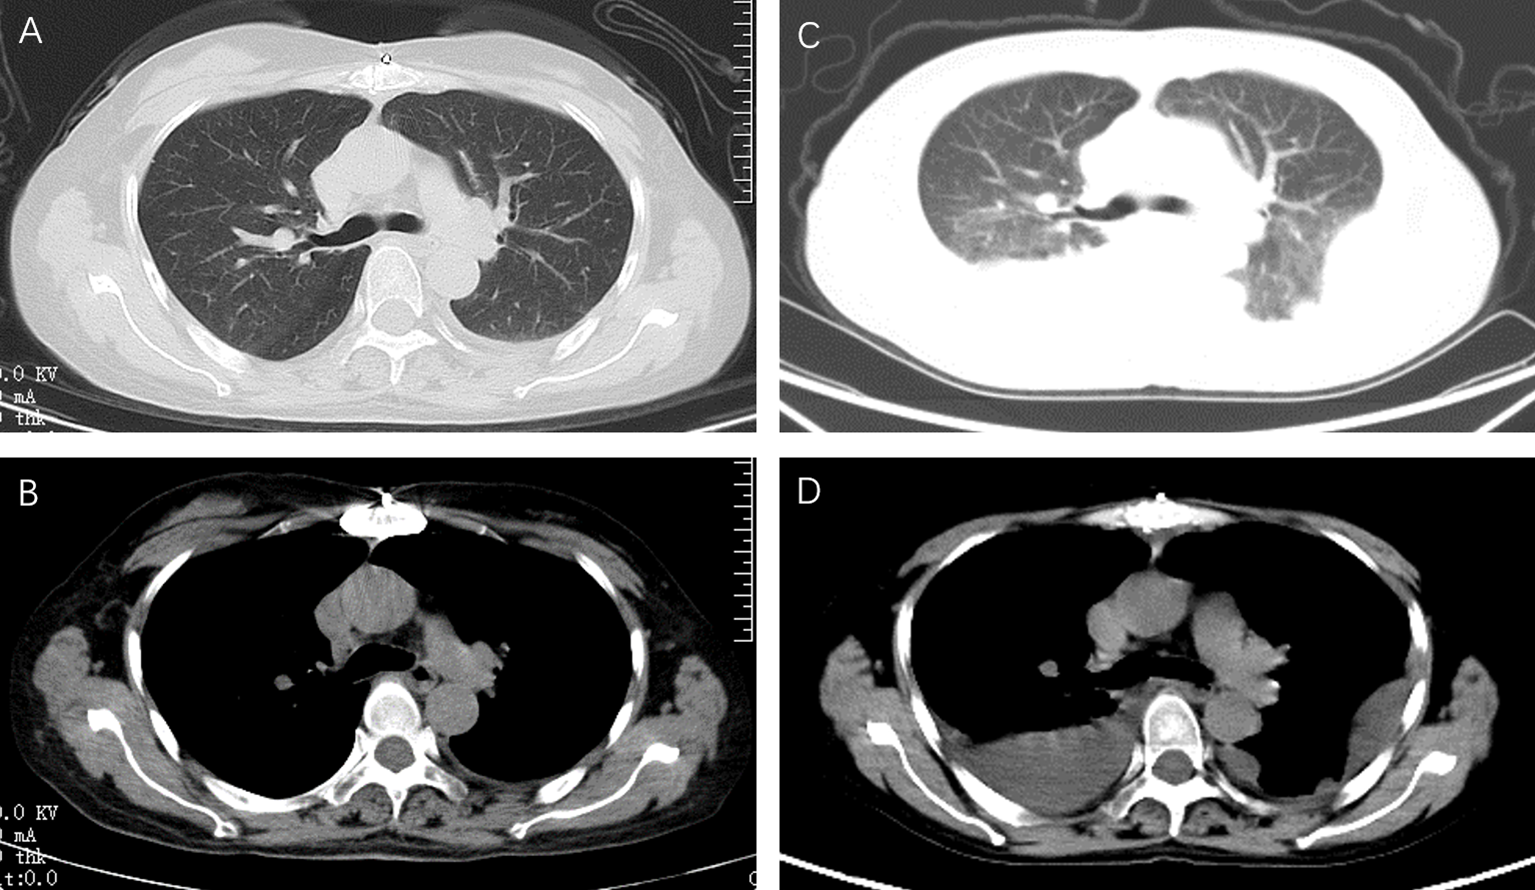

Figure 1

Chest computed tomography at different time points. In the patient with myasthenia gravis after thymoma surgery, a small left pleural effusion was noted on a transverse axial chest CT during regular follow-up (A, B). According to all examinations, the neurologist thought that the chest tightness was due to the recurrence of myasthenia gravis. Methylprednisolone (40mg per day) combined with gamma globulin (400mg per kg) was given. After three days of treatment, the patient's dyspnea worsened. A chest CT was taken again, showed a new bilateral pleural effusion (C, D).

According to the above examination, the neurologist thought that the chest tightness was due to the recurrence of myasthenia gravis. Methylprednisolone (40 mg/day) combined with gamma globulin (400 mg/kg) was given. After 3 days of treatment, the patient’s dyspnea worsened. A chest CT was taken again and showed a new bilateral pleural effusion (Figure 1). Laboratory tests showed a serum albumin concentration of 28.7 g/L. Albumin supplements in combination with diuretics were given because it was thought that bilateral pleural effusions were associated with low serum albumin. However, the patient’s dyspnea was not relieved, and pleural ultrasound showed that there was still a moderate amount of pleural effusion.